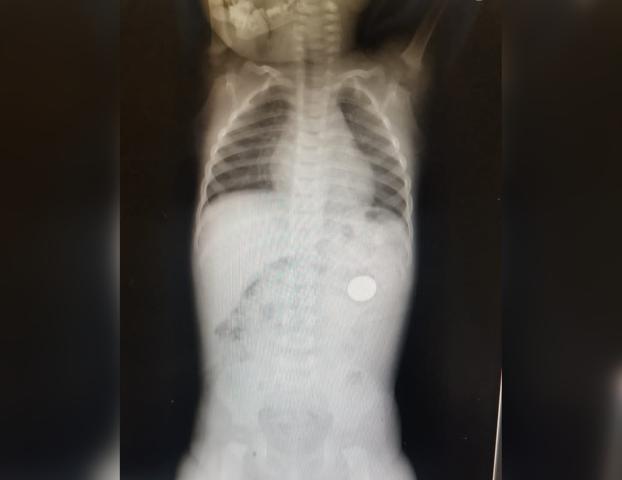

В Уфе врачи извлекли из полуторагодовалого ребенка монету